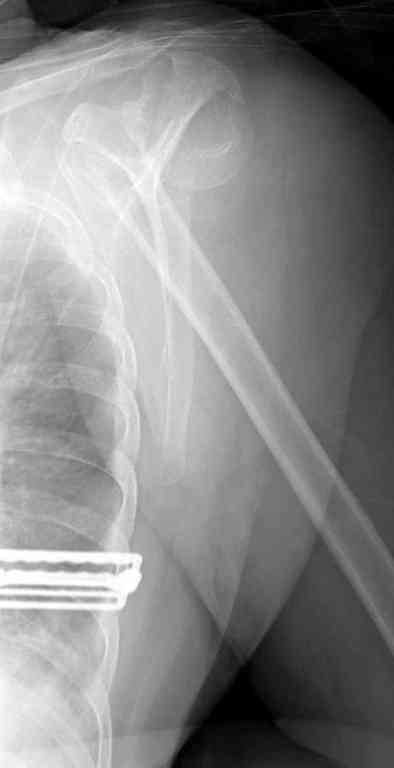

Неправильно выбранная тактика по фиксации или технические ошибки во время операции могут привести к серьезным осложнениям. Здесь привожу

пример из нашей практики, вроде обычный перелом шейки, фиксированный популярным методом "Сиэтла" - множественными спицами 2.8 мм с резьбой на конце.

При первичном осмотре в поликлинике через 3 недели обнаружили миграцию двух спиц, срочно госпитализированному на второй день перед операцией на всякий случай сделали снимок, одна спица находилась под ключицей в шейном отделе (на снимке).